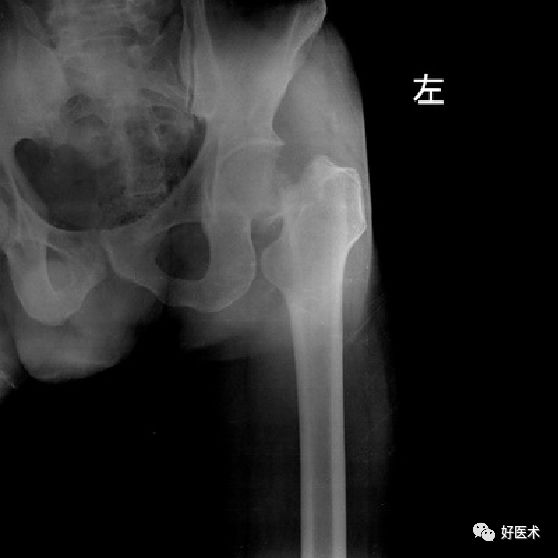

患者,男,69岁,因“摔伤致左髋部疼痛伴活动受限3小时”为主诉于今年10月12到我院急诊科就诊。急诊行X线片检查示:“左侧股骨颈骨质连续性中断”。

Garden分型?

Ⅳ型

内固定 OR 髋关节置换?

髋关节置换

全髋 or 半髋?

股骨头置换

骨水泥 OR 非骨水泥?

非骨水泥假体